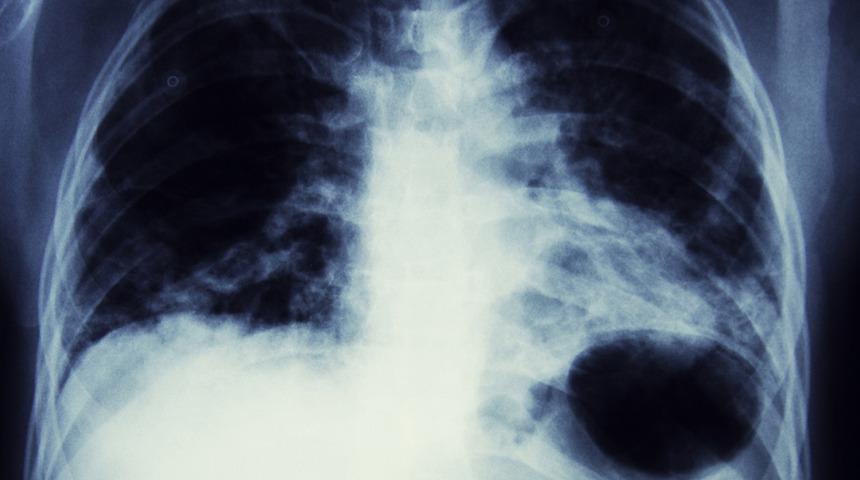

En çok hayati risk taşıyan tür: Akciğer kanseri belirtileri nelerdir?

En çok hayati riske yol açan kanser türü olan akciğer kanseri; inatçı öksürük, akciğer enfeksiyonu, nefes darlığı, ses kısıklığı, göğüs ağrısı ve balgamda görülen kan ile kendisini belli ediyor. Akciğer kanserinden korunmak için tütün ve ürünlerinden uzak durulması gerekiyor. Gelişen tıbbi ve teknolojik gelişmeler ile erken teşhis ve tedavi olanakları sayesinde hastalarının tedavi konforu ve yaşam kalitesi artırabiliyor. Memorial Şişli ve Bahçelievler Hastaneleri Göğüs Cerrahisi Bölümü’nden Prof. Dr. Adnan Sayar, akciğer kanserinin nedenleri, belirtileri ve hastaya özel modern tedavi yöntemleri hakkında bilgi verdi.

Küçük hücreli dışı ve küçük hücreli akciğer kanseri olmak üzere iki çeşidi bulunan akciğer kanseri tümörleri, akciğer dokusunun kendi hücrelerinin kuralsız ve sınırsız bir şekilde çoğalması ile oluşmaktadır. Zamanla büyüyüp kitle haline gelen bu hücreler çevre doku ve organlara yayılabilmekte, kan dolaşımına yolu ile diğer organlara da sıçrayabilmektedir.